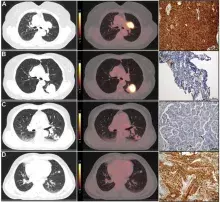

Pierwsza z prac, opublikowana w czasopiśmie Journal of Translational Medicine (IF=7,5) dotyczy nieinwazyjnej oceny ekspresji PD-L1 oraz typu histologicznego niedrobnokomórkowego raka płuca (NSCLC) z wykorzystaniem analizy radiomicznej obrazów PET/CT. W badaniach wykazano, że zastosowanie metod uczenia maszynowego w analizie danych obrazowych umożliwia przewidywanie kluczowych cech biologicznych nowotworu bez konieczności wykonywania inwazyjnych procedur diagnostycznych. Badania przeprowadzono we współpracy z naukowcami z Gdańskiego Uniwersytetu Medycznego oraz Uniwersytetu Medycznego w Łodzi.

1. Tomasik B, Jąkalski M, Bieńkowski M, Teodorczyk J, Sobocki BK, Stawiski K, Burzynski J, Romanowicz G, Dziadziuszko R, Cytawa W, Mieczkowski J. Non-invasive assessment of PD-L1 status and histology in non-small cell lung cancer using 18F-FDG PET/CT radiomics. J Transl Med. 2026 Mar 18. doi: 10.1186/s12967-026-08029-w

fot. z publikacji 1